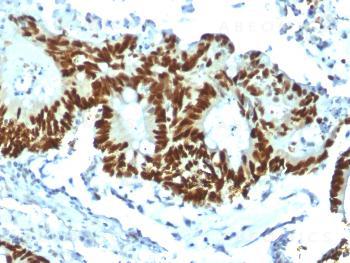

Anti-p53 Tumor Suppressor Protein Monoclonal Antibody(Clone: TP53/1799R)

Fig. 1: Formalin-fixed, paraffin-embedded human Colon Carcinoma stained with p53 Recombinant Rabbit Monoclonal Antibody (TP53/1799R).

Flow Cytometry (1-2ug/million cells); Immunofluorescence (1-2ug/ml); Western Blot (1-2ug/ml); ,Immunohistochemistry (Formalin-fixed) (1-2ug/ml for 30 minutes at RT),(Staining of formalin-fixed tissues requires heating tissue sections in 10mM Tris with 1mM EDTA, pH 9.0, for 45 min at 95 °C followed by cooling at RT for 20 minutes),